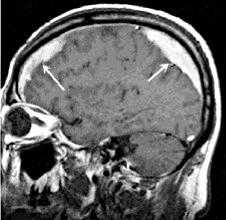

Перечень инструментальных методов диагностики должен быть ограничен только самыми необходимыми и экстренными исследованиями. Раньше он включал эхоэнцефалографию и люмбальную пункцию. Первая позволяла выявить масс-эффект — смещение серединного М-эхо, вторая — повышенное ликворное давление, наличие крови в цереброспинальной жидкости. Сегодня доступность методов нейровизуализации исключает необходимость проведения подобных исследований. В зависимости от показаний пациенту проводится МРТ или КТ головного мозга, а иногда — оба этих исследования. В экстренных ситуациях существенно сократить время проведения томографии позволяет спиральная КТ мозга.

КТ головного мозга дает возможность установить вид, расположение и размер внутричерепного образования, оценить степень дислокации церебральных структур и диагностировать наличие отека мозга. Перфузионная КТ позволяет оценить церебральную перфузию и кровоток, выявить вторичную ишемию. МРТ головного мозга более чувствительна в определении участков мозговой ишемии и очагов ушиба, направления дислокации мозговых тканей. Диффузионно-взвешенная МРТ дает возможность исследовать состояние проводящих путей мозга, установить степень их компрессии.

МРТ ГМ. Сдавление височной доли (зеленая стрелка) головного мозга объемным образованием (красная стрелка)